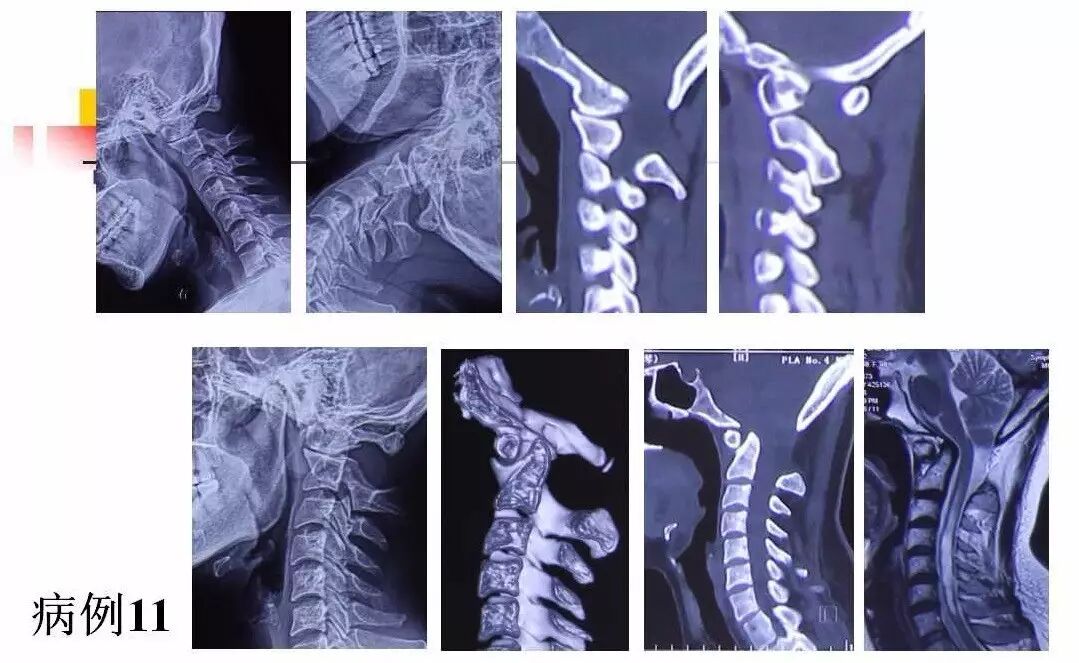

在脊柱神经外科、显微神经外科和颅底肿瘤外科前沿研究和临床诊治领域有着扎实的基础,为全国首批获得脊柱神经外科医师培训认证的神经外科医生。擅长颈椎病、椎管肿瘤及各种脊柱疑难疾病的诊治、脑肿瘤微创手术,尤其擅长颈椎退行性疾病的手术,率先在国内开展了颅底凹陷后路复位、颈前路减压融合等高难度手术,多年来收治了来自全国各地的大量患者,疗效达到国内领先水平。